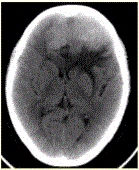

问题 患者女,68岁。头痛、恶心2周,加重2d。头CT显示如下图。 关于该病的描述,正确的是

选项 A.病变与脑实质边界不清,跨越大脑镰提示病变位于轴内 B.病变密度较高,提示内部伴发出血 C.病变邻近颅骨可见骨质肥厚,支持病变位于轴外 D.病变形态不规则,周围水肿明显,支持病变位于轴外 E.为进一步明确诊断,需增强检查 F.CT平扫可以评价病变与硬脑膜的关系

答案 ABCE